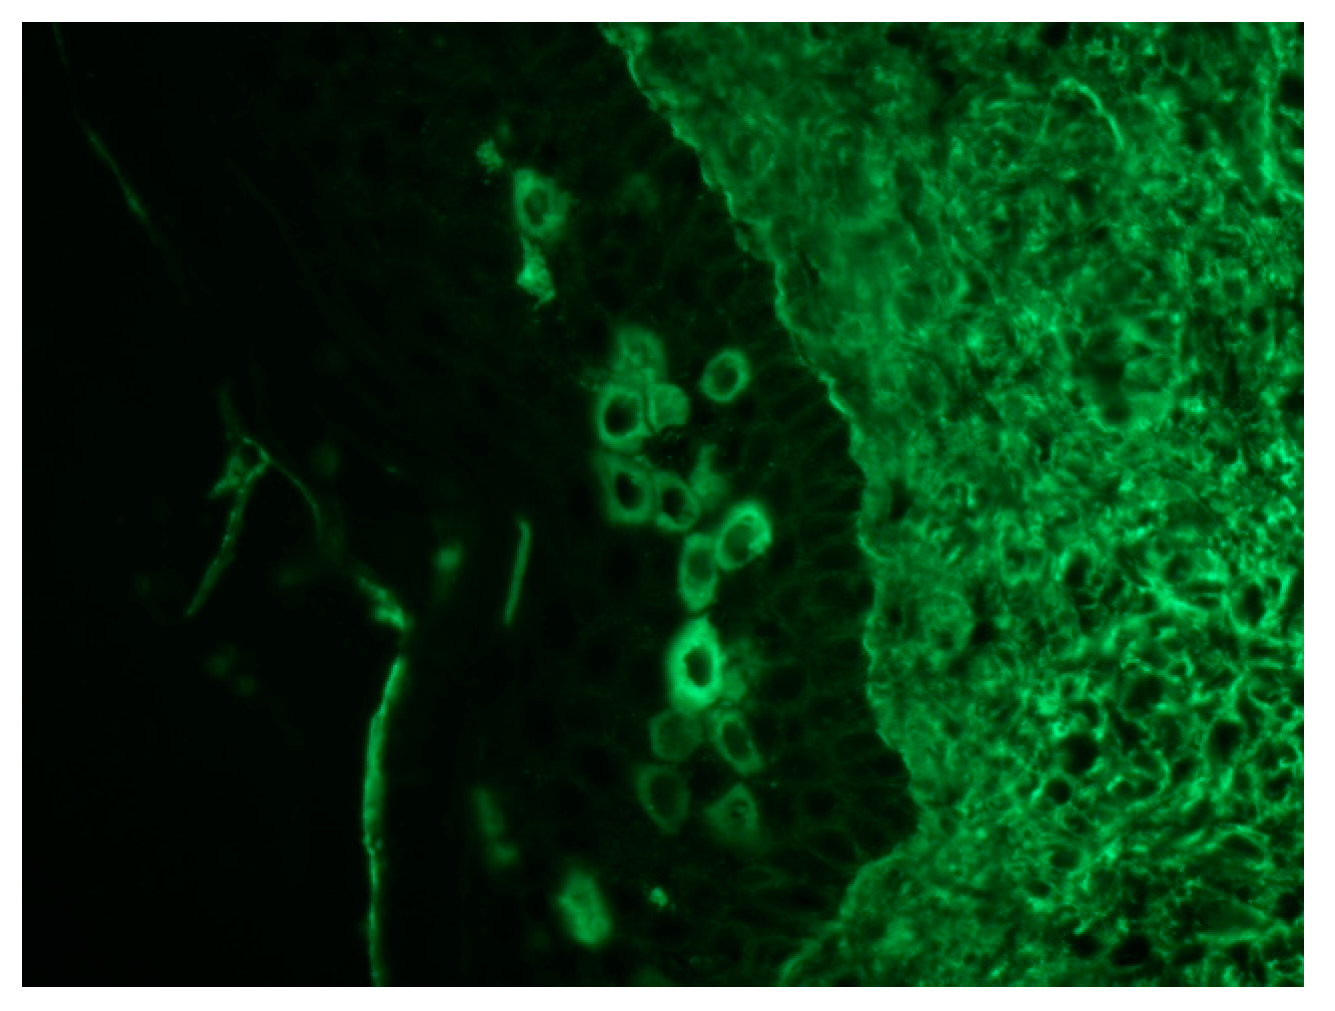

8. Immunological Studies

| Direct immunofluorescence | Combined presence of IgG and complement (C3) granular-linear deposition within the epidermal intercellular spaces and along the basement-membrane zone |

| Indirect immunofluorescence | Presence of circulating antibodies that target the intercellular zone of stratified squamous or transitional epithelia |

| DIF | Combined presence of IgG and complement (C3) granular-linear deposition within the epidermal intercellular spaces and along the basement-membrane zone | |

| IIF | Presence of circulating antibodies that target the intercellular zone of stratified squamous or transitional epithelia | |